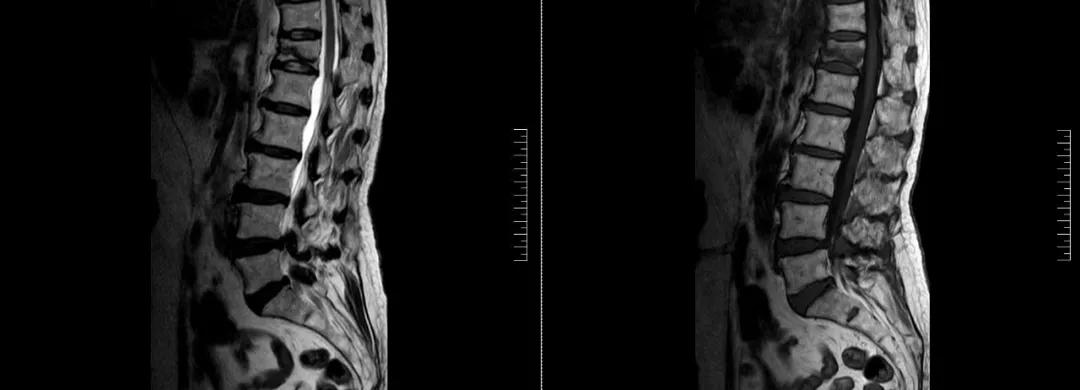

術(shù)前磁共振檢查提示腰1椎體新鮮壓縮性骨折

術(shù)后復(fù)查CT可見骨水泥彌散充分